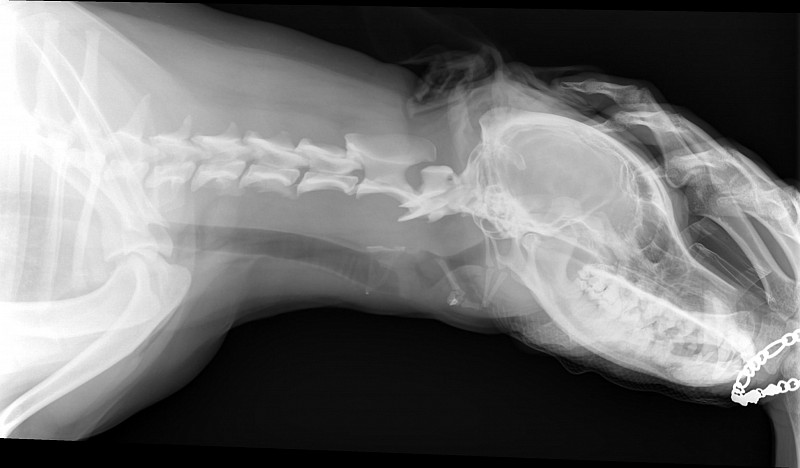

Рентгеновские снимки анатомии собак: строение и здоровье